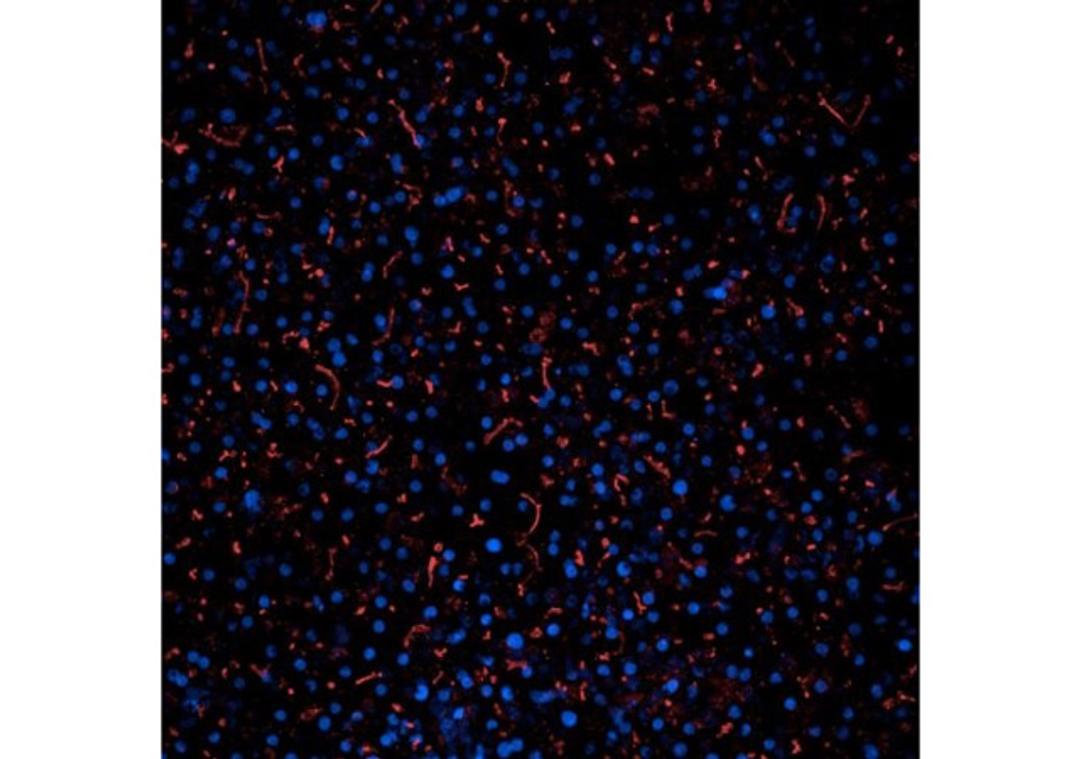

Includes the essential components needed to create the quad-culture Liver-Chip R1: Chip-R1™ Rigid Chips, Pod® Portable Modules, Steriflip Filters, and Emulate-qualified human cells (primary human hepatocytes, liver sinusoidal endothelial cells, Kupffer cells, and stellate cells).

Included Cell Types: Primary human hepatocytes, stellate cells, Kupffer cells, and liver sinusoidal endothelial cells.